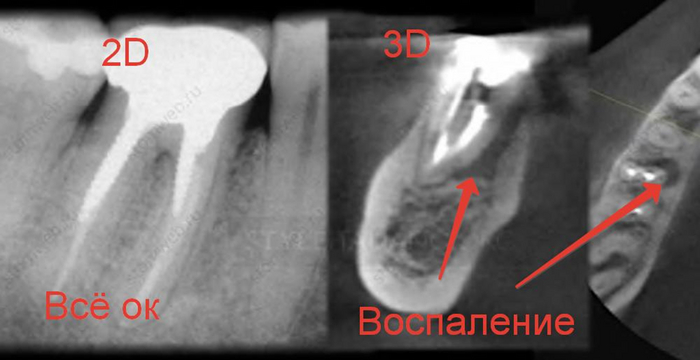

После того, как пациент сделает нормальный трехмерный снимок, с вероятностью 90% мы будем наблюдать один из подобных примеров.

Как вы уже догадались при получении двухмерного изображения трехмерного объекта, его структуры будут накладываться друг на друга. Так как рентген-диагностика заключается в анализе разницы плотности слоев, что выражается на снимках в виде различных оттенков серого, то более плотные слои(белые) могут запросто перекрывать менее плотные(черные), из-за чего точность этой диагностики снижается.

Компьютерная томография «нарезает» объект послойно, позволяя увидеть все структуры под каким угодно углом без искажений. Таким образом мы сможет поставить максимально точный диагноз, определить более точный прогноз зуба, определить расположение будущих и уже установленных имплантатов, определить расположение гайморовой пазухи и нижнего альвеолярного нерва при удалении сложных зубов, определить расположение корней, определить количество каналов в корнях….можно продолжать долго.

Вот ещё примеры.

Поэтому если физрук сказал лыжи в апреле, значит лыжи стоматолог направляет на КТ, то идем на КТ, даже если надо решать вопрос с одним зубом

Некоторые изображения выли взять из статьи Fabio Gorni «CBCT: The dark side of the moon» (styleitaliano), которая была переведена при поддержке компании STOMWEB